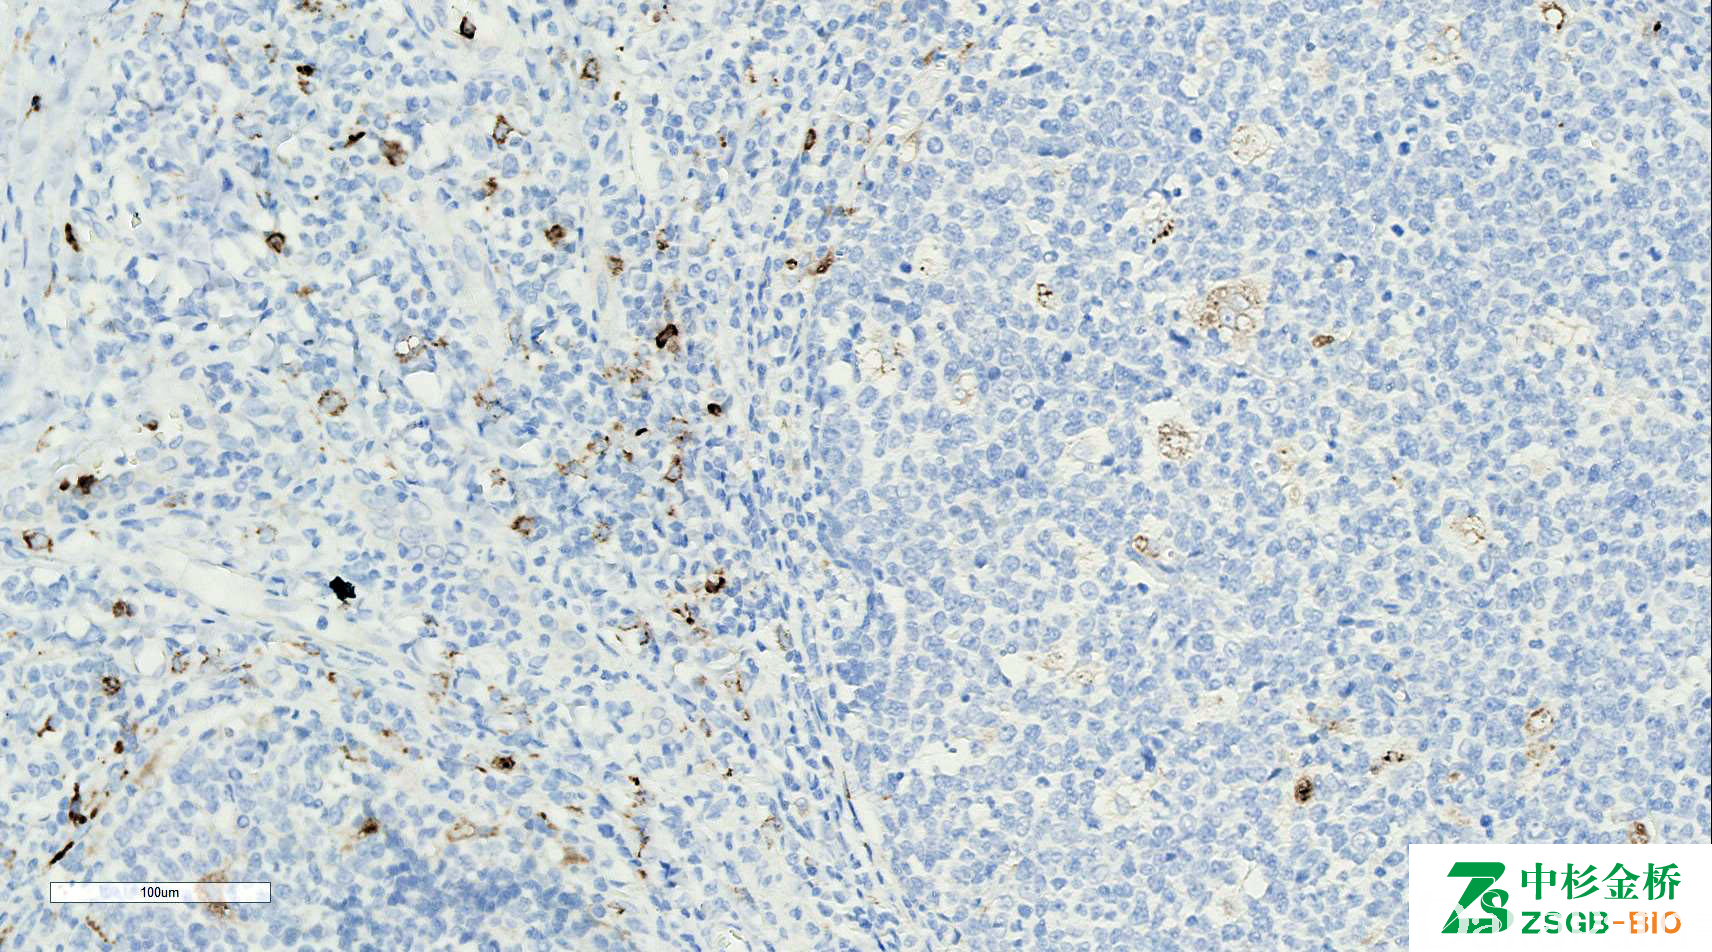

lysozyme

组织细胞的一种酶,可切断细菌细胞壁上胞壁酸间的连接。标记组织细胞、单核细胞及部分上皮细胞。

信号定位: 胞质

用以标记组织细胞、单核细胞;

单核细胞白血病(M4、M5)及髓系肉瘤的诊断。